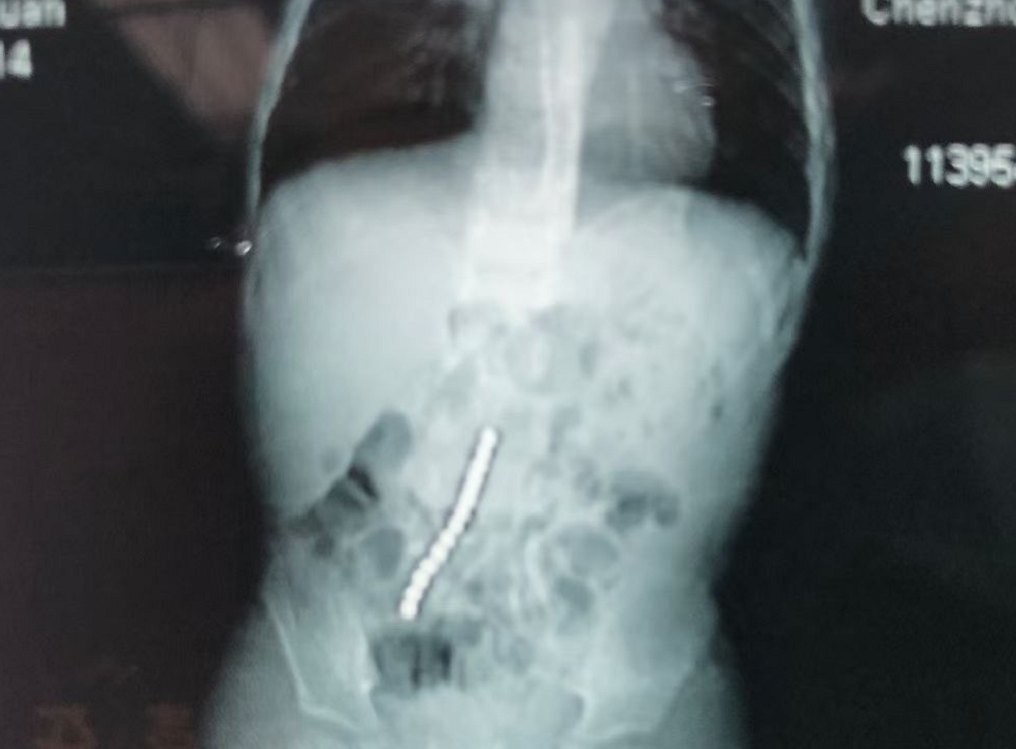

医生经X射线检查,发现军军的消化道内有14颗细小、均匀的球体呈“一”字形排开。随后,其被诊断为消化道磁性异物。

由于磁力珠多,风险大,自行排出可能性小,充分告知风险后,家属签字同意医生手术建议,当天下午滕水生医师手术组为患儿做了急诊手术,术中发现孩子小肠多处穿孔,他小心翼翼找到患儿藏珠的位置,从小肠穿孔处将磁力珠一颗一颗取出,手术持续三个小时,总共取出14颗磁力珠。